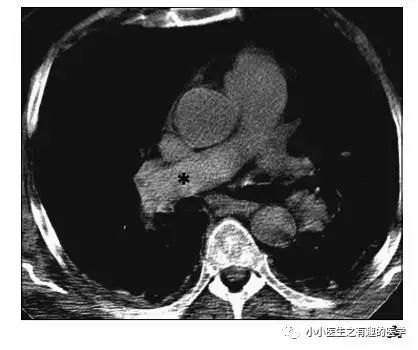

如图,高密度影的那一条。

不怕,有增强CT证实。

是不是很有趣。